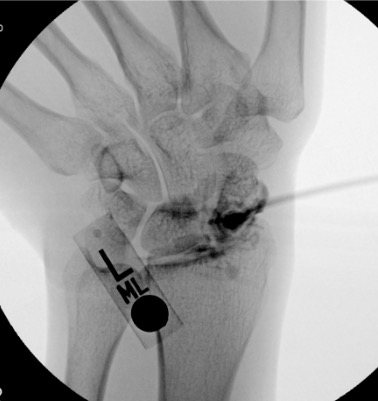

| Wrist | 1–3 mL | Fluoroscopy | Dorsal approach to radiocarpal joint | Lister's tubercle as dorsal reference landmark; radiocarpal joint just distal to radius on AP fluoroscopy; note multiple compartments — radiocarpal, midcarpal, and DRUJ each separate and may require individual injection for arthrography |

Wrist

Needle placementPost-injection